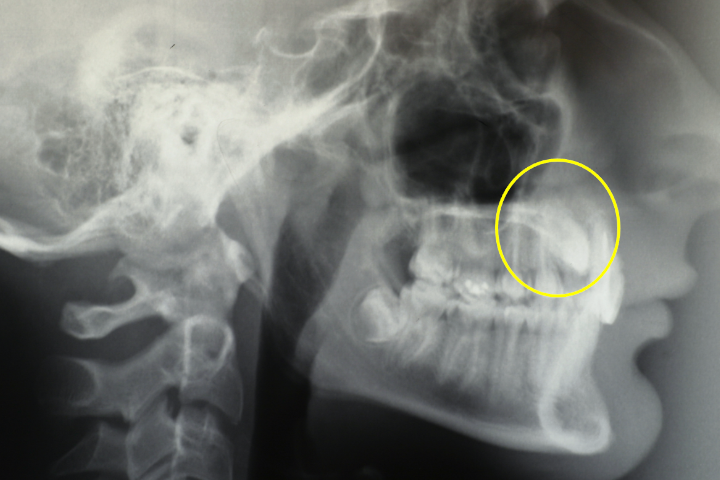

Lewis è un ragazzo di 15 anni con discromia dell’incisivo centrale superiore di destra per pregresso trauma. Una CBCT, prescritta altrove, individua l’esatta posizione dei canini inclusi palatalmente.

All’interno di una cornice scheletrica equilibrata l’occlusione presenta rapporti di I° classe a sinistra, tendente alla II° a destra, con morso coperto anteriore e persistenza dei canini decidui.